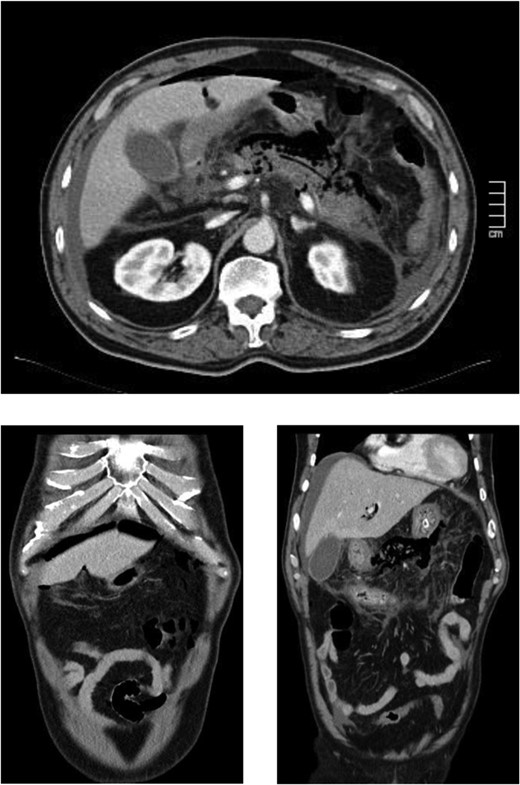

The case report refers to a 62-year-old man with medical history of hypertension, dyslipidemia and previous coronary stent placement. He went to the emergency department with upper abdominal pain with few hours of onset and vomits. The initial serum amylase was 2306 U/L and urinary amylase was 14 231 U/L. He met only one Ranson criteria at admission (Table 1). The first CT showed signs of a non-complicated acute pancreatitis (Fig. 1). He remained under surveillance and suffered clinical deterioration with progressive abdominal pain and tenderness and for this reason he was admitted on the intensive care unit (with an APACHE II score at admission of 15) where he progressed rapidly to multiple organ failure in <24 h. Due to this sudden worsening, with suspicion of a bowel perforation, a new CT scan was performed, showing significant gas dissection through the fascial planes with pneumoperitoneum and pneumoretroperitoneum (Fig. 2), however, without extraluminal contrast leakage evidence. This radiological gaseous pattern could not exclude a visceral perforation and raised the possibility of an anaerobe gas-producing bacteria presence. This sudden and progressive clinical deterioration together with an uncertain perforation or even an infected pancreatitis requiring for drainage motivated the beginning of empiric antibiotherapy with Meropenem and Metronidazol and an exploratory laparotomy on the operating room.